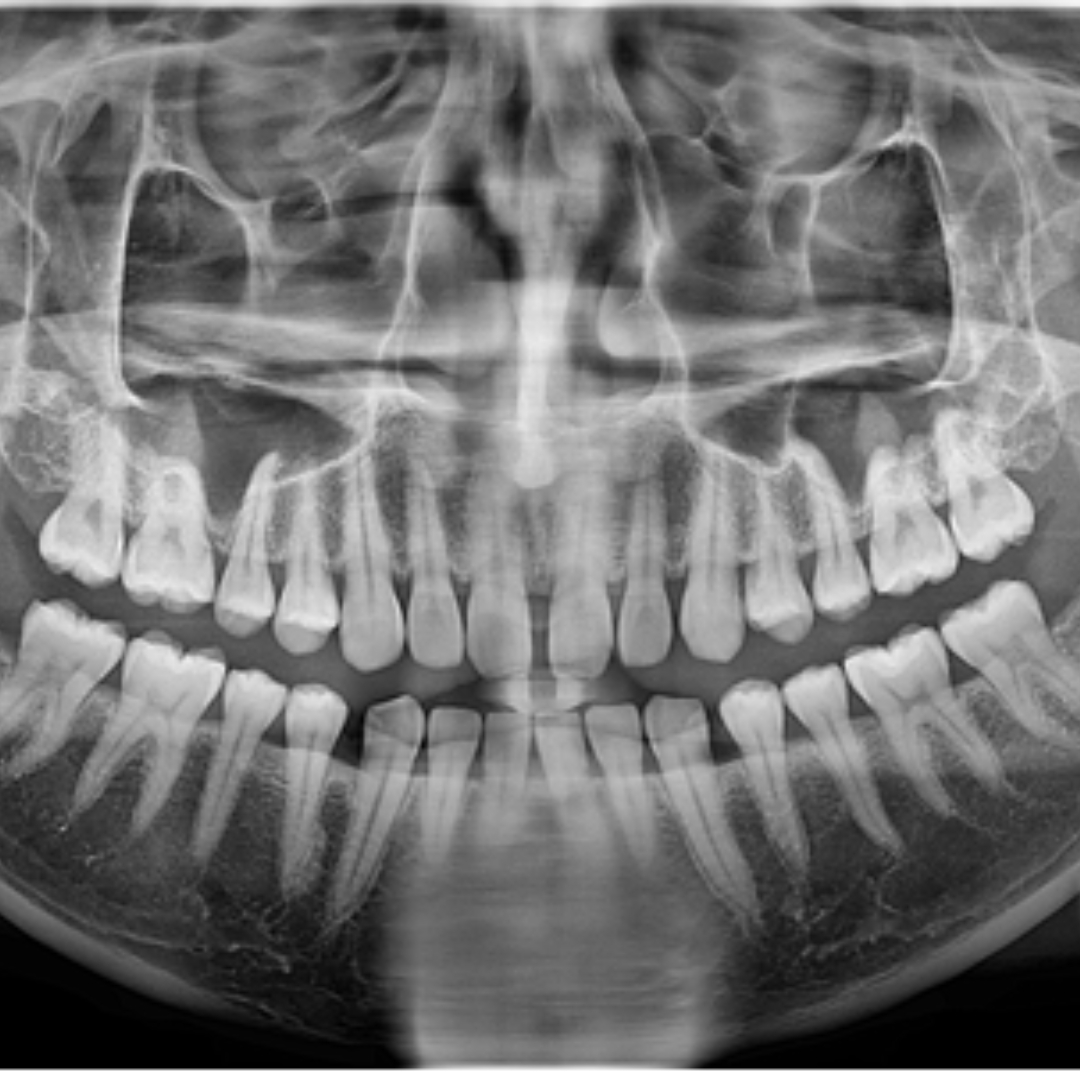

돌출입, 덧니의 발치 교정 치료 증례

돌출입과 덧니를 고민으로 내원하신, 10대 청소년 환자 분의 증례를 소개드리겠습니다.촬영일시 : ..